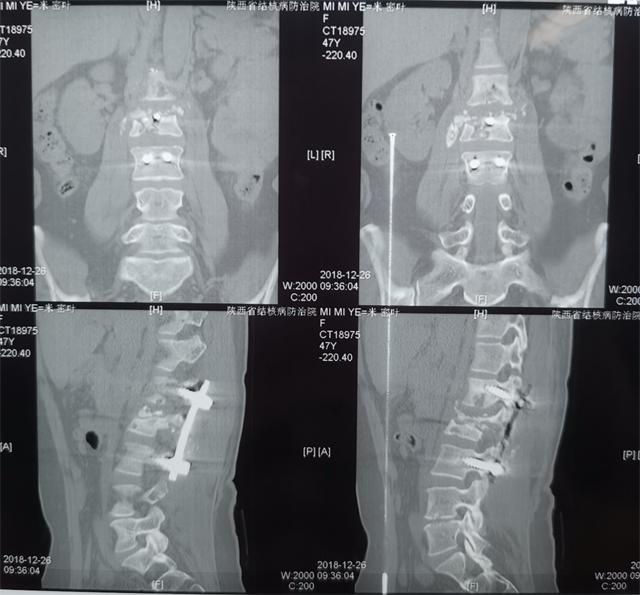

2019年1月25日上午,全国著名结核病专家北京胸科医院骨科秦世炳主任莅临我院外科开展临床协作指导工作。秦主任参加了我院外科的晨交班会,在会上,他首先分享了他们先进的理论和工作经验,并热心的对我外科的临床科研工作进行了指导。 此后,秦主任针对我科及全院各科所遇到的结核骨科方面的疑难杂症进行了耐心的会诊和一一解答,并亲自为我科收治的一例腰椎结核后路钉棒内固定手术后复发并长期窦道形成的患者进行了手术指导。